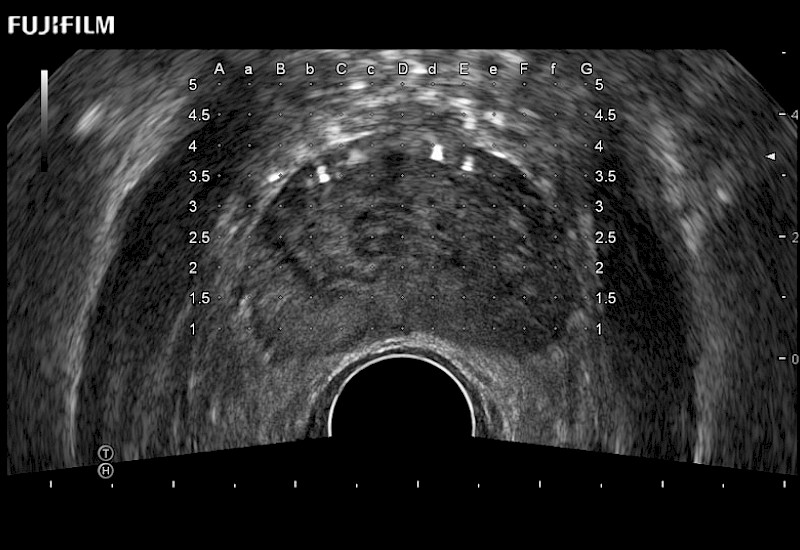

Exclusive 200° FOV end-fire prostate biopsy transducer.

Main Specifications: